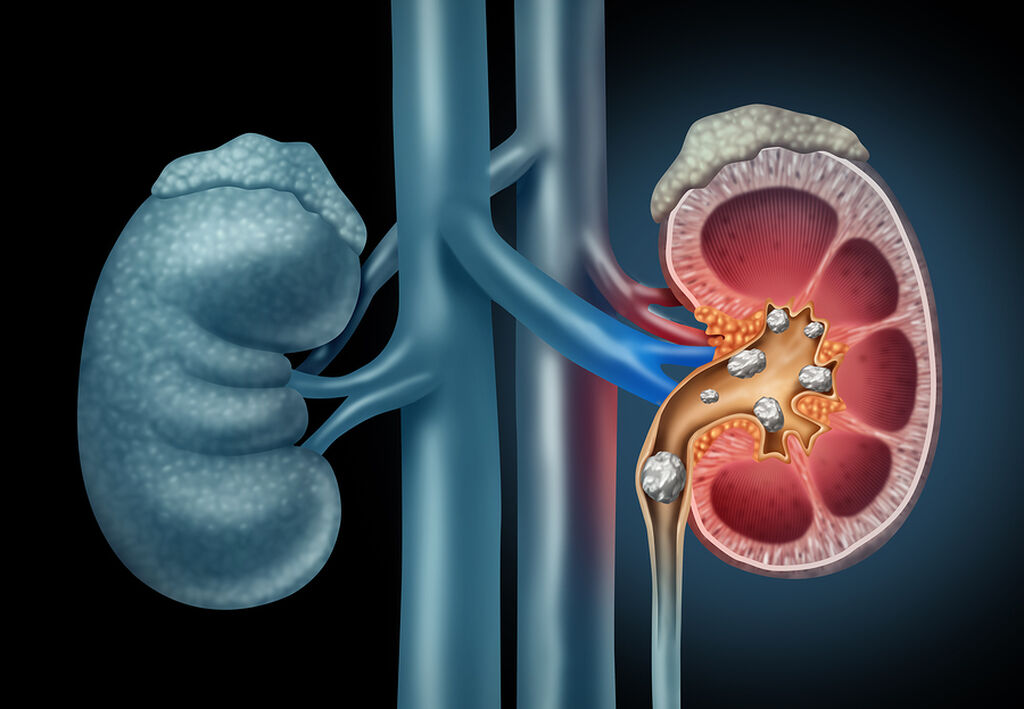

4. Ουρολογικές παθήσεις, όπως είναι οι πέτρες στο ουροποιητικό σύστημα.